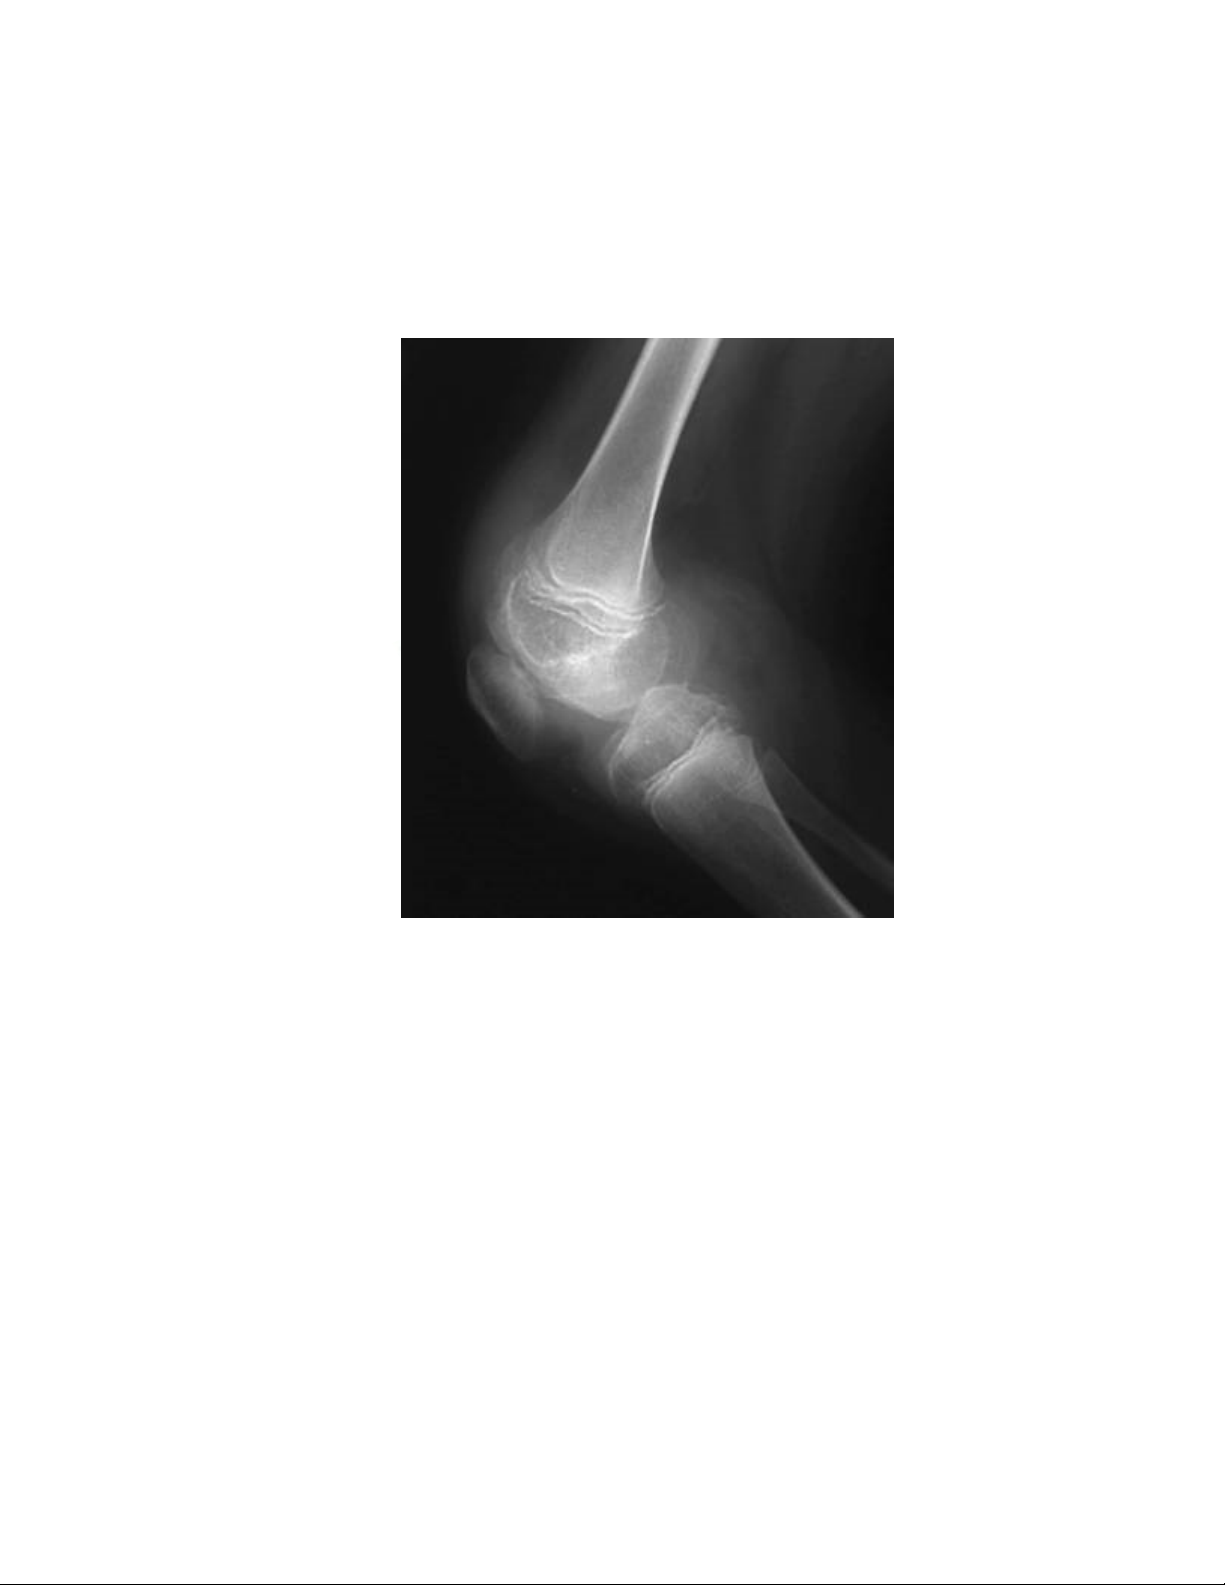

thương nhẹ. Đặc điểm xuất huyết là dám bầm máu dưới da, tụ máu trong cơ, chảy

máu ở khớp, đôi khi có tiểu máu.

- Giữ khớp ở tư thế dễ vận động, phối hợp điều trị phục hồi chức năng vận

động khớp.